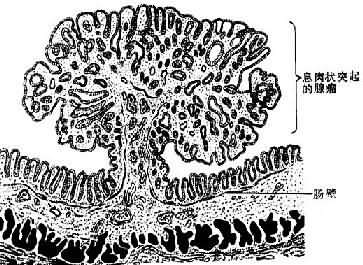

图7-9 皮肤乳头状瘤

2.腺瘤(adenoma)是由腺上皮发生的良性肿瘤,多见于甲状腺、卵巢、乳腺、涎腺和肠等处。粘膜腺的腺瘤多呈息肉状(图7-10),腺器官内的腺瘤则多呈结节状,且常有包膜,与周围正常组织分界清楚。腺瘤的腺体与其起源腺体不仅在结构上十分相似,而且常具有一定的分泌功能。不同这外仅在于腺瘤的腺体大小、形态较不规则,排列也比较密集。发生于有小叶和导管结构的器官的腺瘤,其小叶结构往往缺如或不明显,亦无导管形成,故不能将其分泌物排出。

图7-10 肠的息肉状腺瘤模式图

(4)息肉状腺瘤(polypous adenoma) 发生于粘膜,呈息肉状,有蒂与粘膜相连,多见于直肠(图7-10),其中表面呈乳头状或绒毛状者恶变率较高。本瘤亦见于结肠、胃等处,结肠多发性腺瘤性息肉常有家族遗传性,不但癌变率很高,并易早期发生癌变。